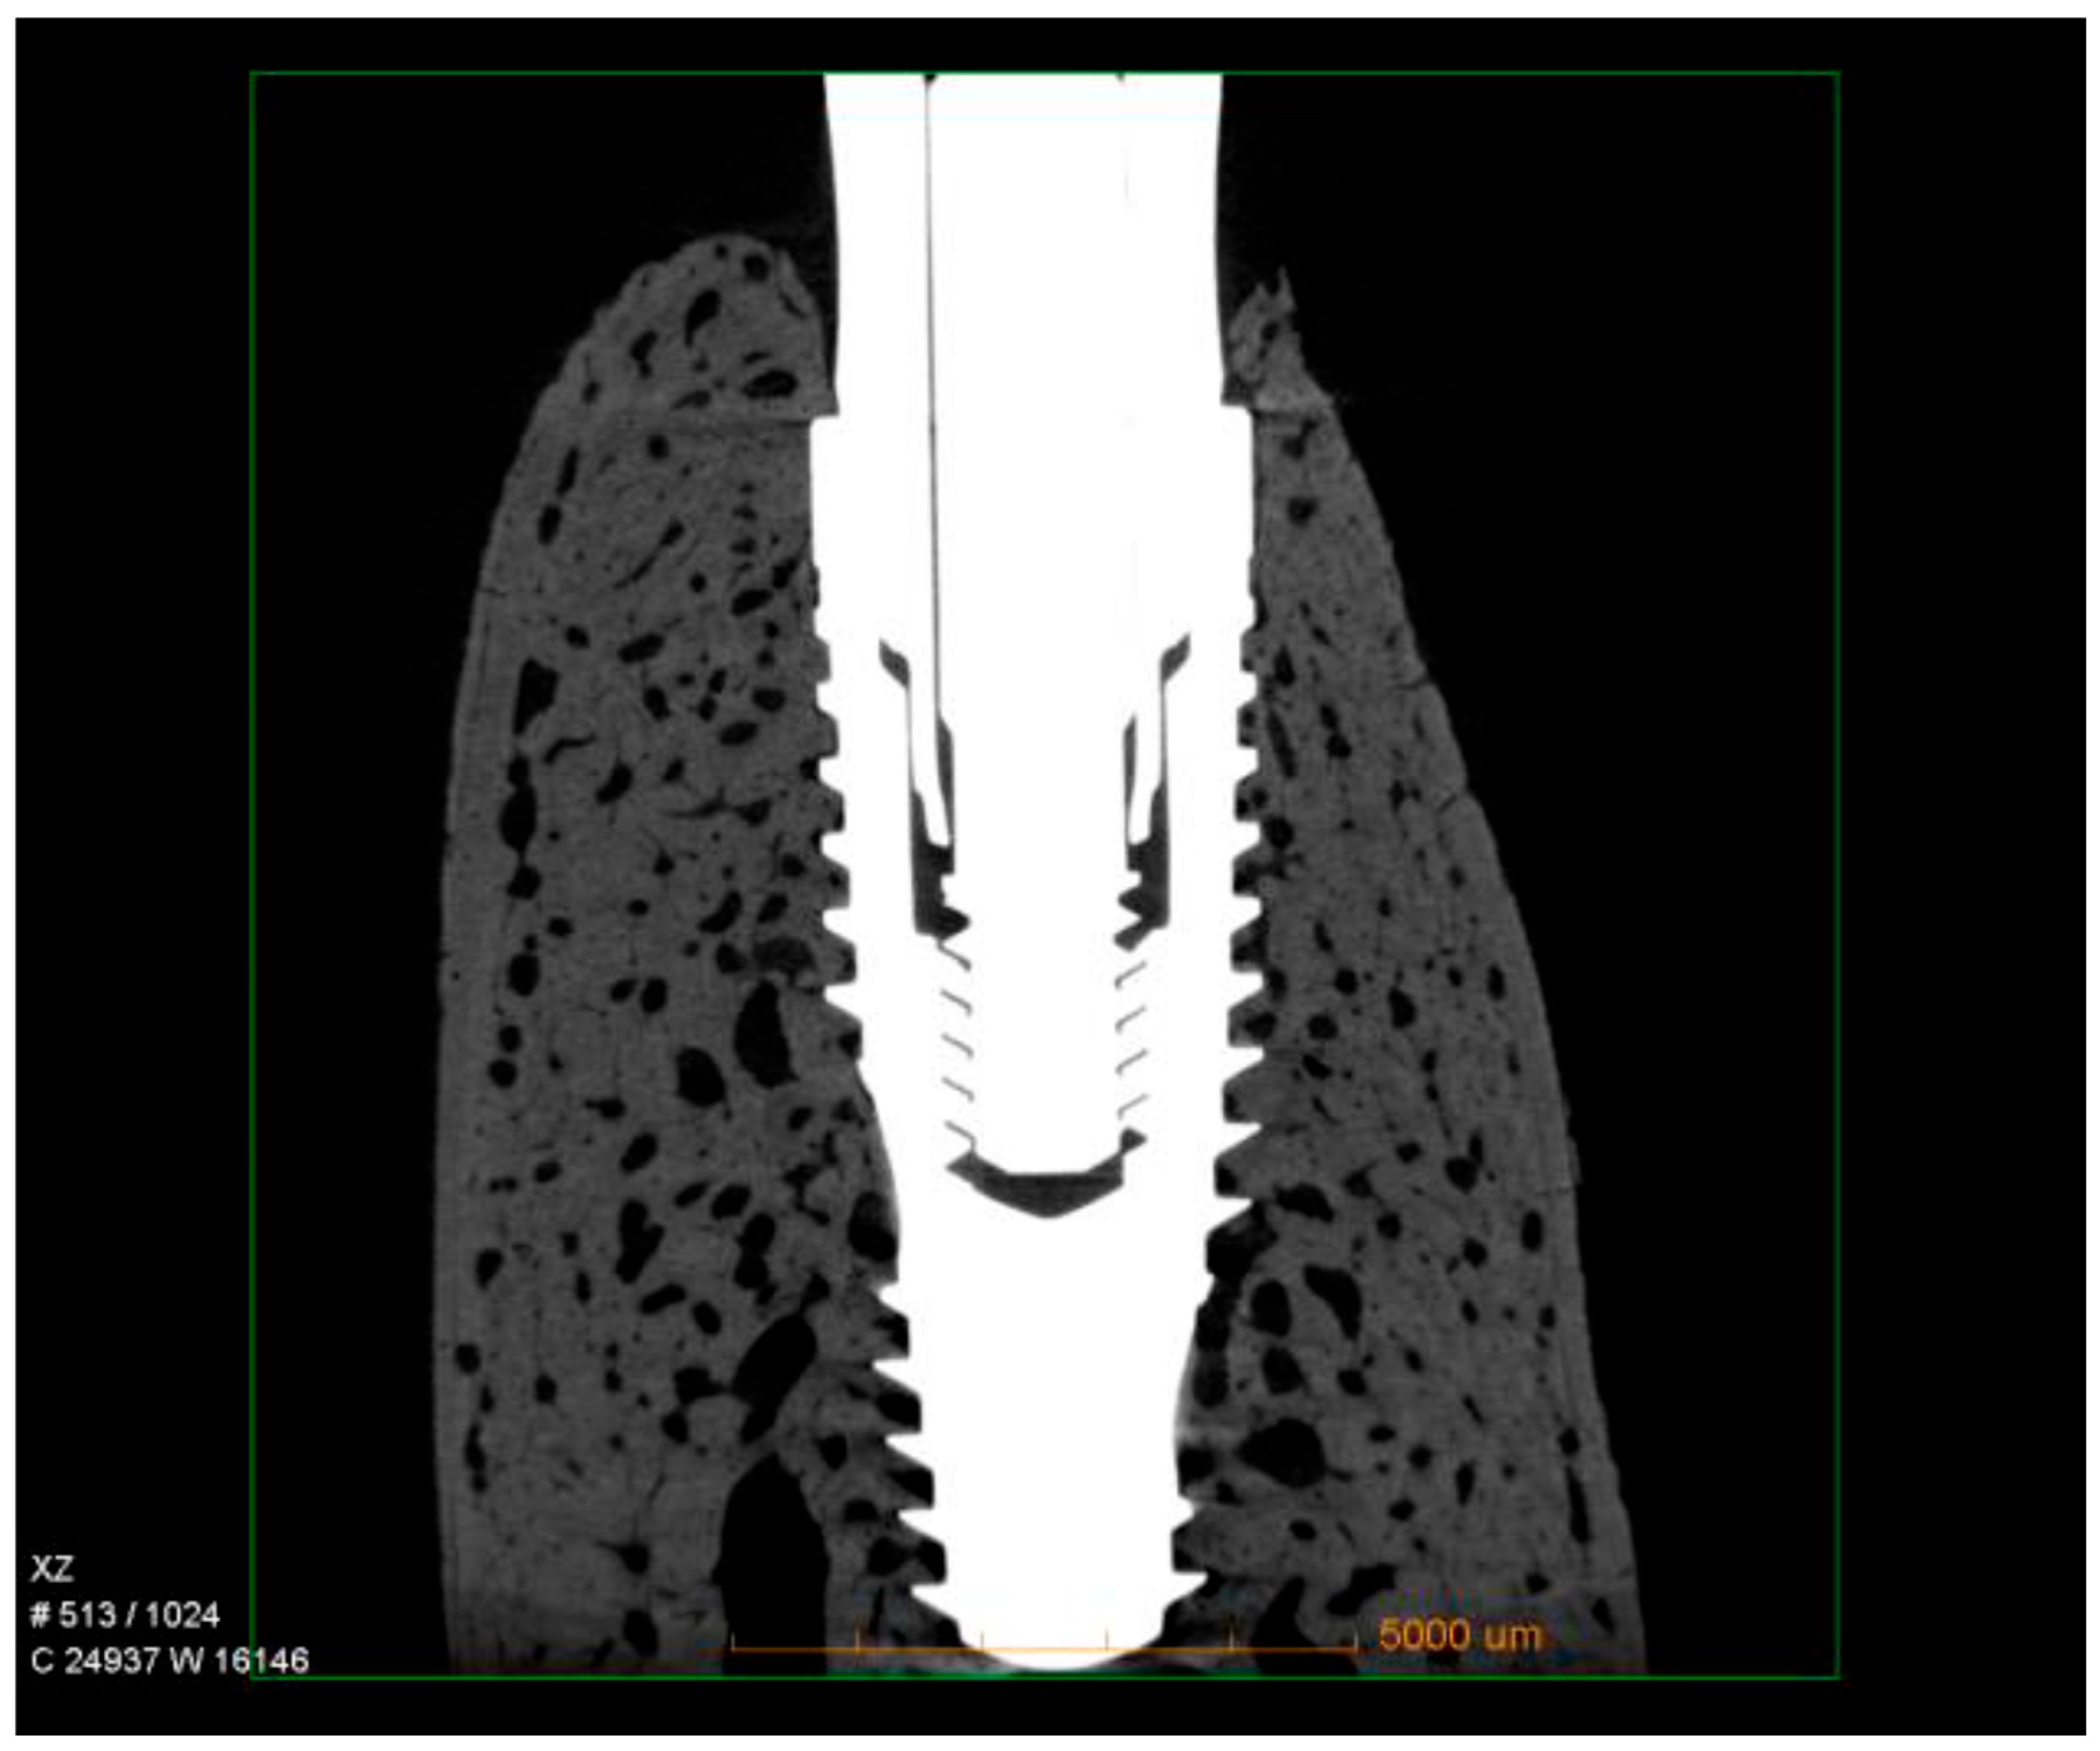

2.5. Micro-CT

3.1. Histomorphometry and Micro-CT

3.2. Vertical Measurements